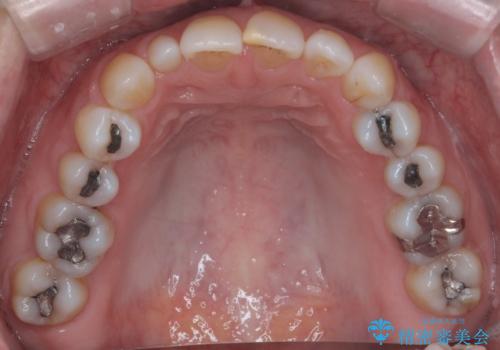

- 右上の2番目の前歯がとがった形をしていたため、セラミックで形を整えています。

- 右上2 15.4万円(内訳 ジルコニアクラウンスペシャル 13万円、仮歯 1万円)費用は治療当時の料金となります

下の前歯とのかみ合わせが切端咬合だったため、前歯の部分矯正も併せて行っています。(費用別途)